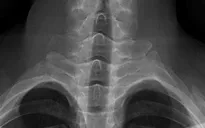

Lý giải về cơ chế sinh bệnh, bác sĩ Trần Minh cho biết đây là hệ quả của hội chứng mất cân bằng cơ, hay còn gọi là hội chứng chéo trên. Việc duy trì tư thế tĩnh quá lâu khi làm việc với thiết bị điện tử khiến các nhóm cơ vùng cổ, ngực và vai rơi vào tình trạng đối nghịch khi một bên co thắt, một bên yếu liệt. Chính sự mất ổn định về lực này đã tạo áp lực tiêu cực lên hệ xương khớp, dẫn đến những thay đổi về mặt cấu trúc và biến dạng cột sống cổ.

Bác sĩ khuyên người dân nên áp dụng quy tắc 90-90-90 (giữ góc 90 độ tại hông, đầu gối và khuỷu tay) khi làm việc, đồng thời nghỉ giải lao sau mỗi 45-60 phút. Ngoài ra, cần lưu ý chọn gối ngủ có độ cao vừa phải 8-10 cm để giữ cột sống thẳng. Đặc biệt, bác sĩ cảnh báo tuyệt đối không tự ý bẻ cổ tạo tiếng kêu, vì thói quen này có thể trực tiếp dẫn đến thoát vị đĩa đệm.